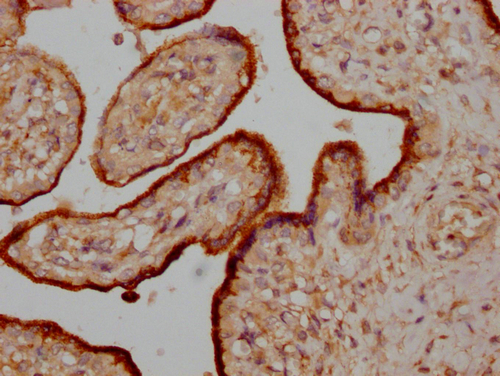

IHC image of CSB-PA017269LA01HU diluted at 1:200 and staining in paraffin-embedded human placenta tissue performed on a Leica BondTM system. After dewaxing and hydration, antigen retrieval was mediated by high pressure in a citrate buffer (pH 6.0). Section was blocked with 10% normal goat serum 30min at RT. Then primary antibody (1% BSA) was incubated at 4°C overnight. The primary is detected by a Goat anti-rabbit IgG labeled by HRP and visualized using 0.05% DAB.